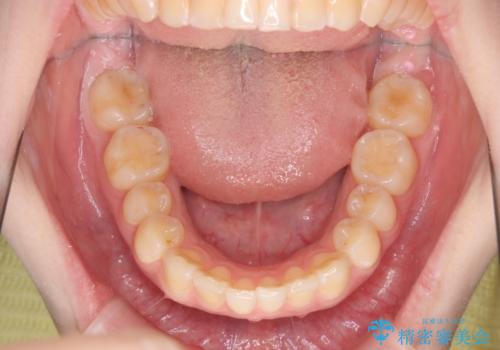

マウスピース矯正で行う出っ歯の治療

- 飛び出したように見える前歯の改善を求めて来院されました。

元々、セラミッククラウンですぐに歯並びを改善したいと希望されていましたが、目立たないマウスピース矯正治療のご提案を行なったところ矯正治療による歯並びの改善を選択されました。

矯正治療を行ったことで出っ歯の改善とともに安定した噛み合わせも手に入れることができました。